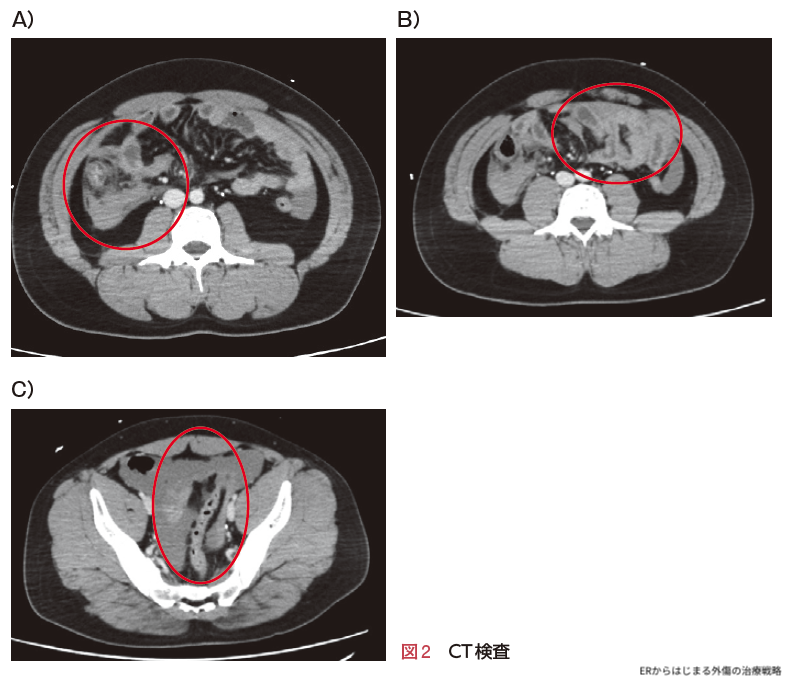

上行結腸周囲に腸間膜血腫,後腹膜血腫を認めました(図2A ○).一部小腸には拡張像があります(図2B ○).また膀胱直腸窩に液体貯留を認めます(図2C ○).腹腔内すべてのスライス画像で造影剤漏出像やフリーエアーは認めませんでした.